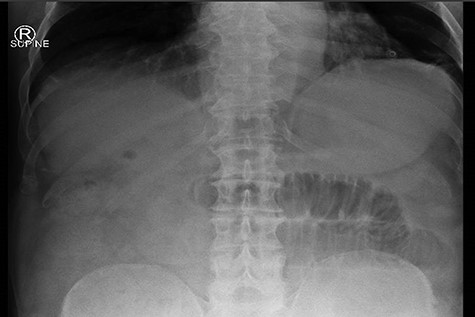

Given that the patient was clinically well, he was managed conservatively overnight with a nasogastric tube and intravenous fluid therapy. The CT scan was closely reviewed by the surgical team the following day and noted the presence of gas within the gallbladder, which was not commented upon by the radiologist (Fig. 2). Furthermore, SBO transition point appeared to be in the distal ileum, where a 3-cm “soft tissue” mass was seen (Fig. 3). His previous CT scan that diagnosed his chronic cholecystitis demonstrated a 3-cm gallstone within the gallbladder, which was not seen on the current CT. The findings of gas within the gallbladder in the setting of SBO and a mass of similar size to the known gallstone raised the suspicion for gallstone ileus. The patient then underwent a laparotomy and enterotomy for a 43-mm gallstone impacted in the distal ileum (Fig. 4). Apart from an episode of ileus, he made a full recovery post-operatively and was discharged home, with an outpatient follow-up in the surgical clinic.

In this scenario, this patient was known to have gallstones and a virgin abdomen, so gallstone ileus was always a possibility. It was the finding of gas in the gallbladder on CT that prompted the surgeons to consider the diagnosis. It is important to note that the diagnosis of gallstone ileus could not be made on plain abdominal radiography, despite the fact that the X-ray was consistent with SBO. This is due to very little air in the biliary tree and only a small bubble in the gallbladder. The gallstone was not calcified and appears of soft tissue density, and was invisible on plain X-ray. Therefore, CT abdomen should be the investigation of choice for suspected gallstone ileus, due to superior sensitivity of CT to detect small amount of gas within the biliary tree and to identify an intra-luminal foreign body of soft tissue density. Neither of these things is possible with plain radiology.